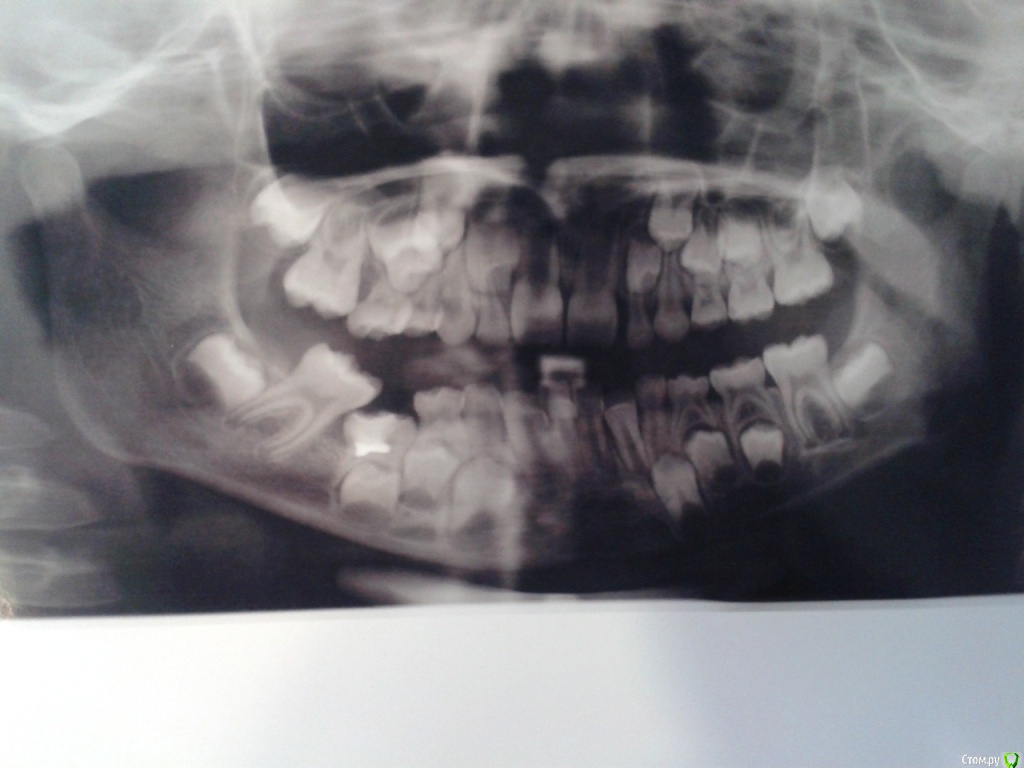

С лета 2014 г. начал прорезываться нижний правый зуб 5-ка. До настоящего времени зуб находится по своей высоте в десне. Так как этот зуб по площади своей поверхности находился на 30-40% под десной, то начал появляться кариес. Ребенку было три года и вычищать досконально было очень тяжело. Заметив темное пятно, обратились к терапевту. Нам без снимка сказали, что это пульпит и тому подобное. Кроме того, с тех пор ребенок отказался посещать врача – испугалась. Грубое обращение. Впоследствии образовалась полость. Кариес. Обратились к другому терапевту, который поставил диагноз «пульпит». Сделали снимок, который показал анкилоз. Ортодонт и терапевт сомневались в лечении зуба, предлагая его удалить. Ортодонт высказывала опасения, что удаление тоже опасно, так как прямо под корнями этого зуба расположен постоянный зуб. Говорила, что зуб уже никогда не прорежется. Терапевт предлагала попробовать спасти зуб. Убрать нависающую часть десны и пролечить пульпит, поставить пломбу.

По снимку сказали нет зачатков каких-то постоянных зубов. Это наследственное по моей линии. Глубокий прикус, в дальнейшем требуется ортодонтическое лечение

Прилагаю снимки. Один до того, как прорезался наклоненный зуб. Второй - после его прорезывания и лечения зуба с анкилозом. Прошу прощения за качества некоторых снимков.

Пломба на снимках имеет розовый, почти красный цвет.